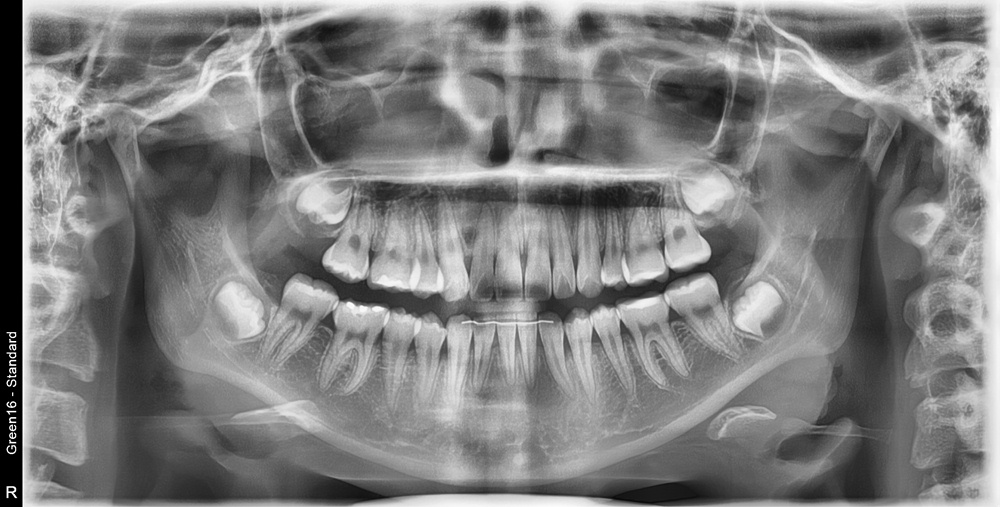

치료 후 사진입니다.